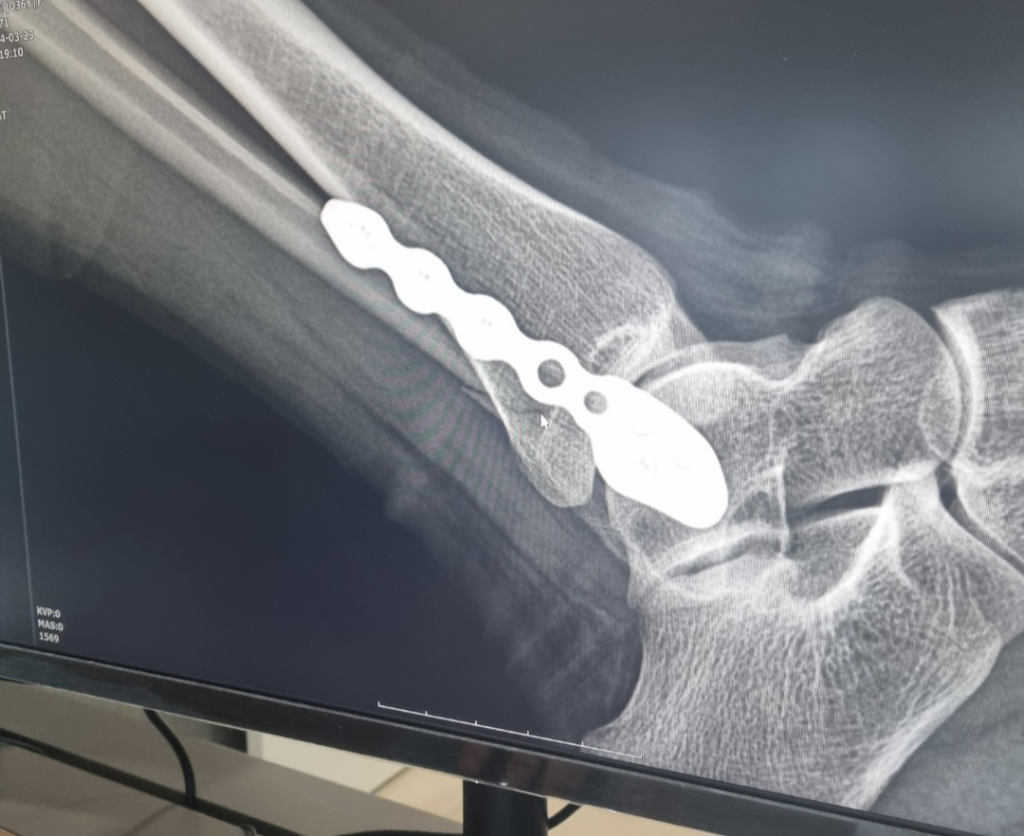

첫 번째 사진은 비골골절 직후 수술 전 사진이고

두 번째, 세 번째 사진은 플레이트를 심은 후의

사진입니다.

두 번째 사진의 마우스 커서 끝이 향해 있는 곳을

보시면 금이 가 있는걸 보실 수 있는데

플레이트 고정이 잘 되어 있는거 맞나요?ㅠㅠ

발 뒷쪽으로 뾰족하게 부서진 부분이

조금 튀어나와서 걱정되어 전문가분들께 여쭤 봅니다.

• 1번 째 사진

• 2번 째 사진

네 저정도의 틈은 신경쓸건 아닙니다.

이미 부러진부분을 그림처럼 딱 맞출순 거의 없습니다..